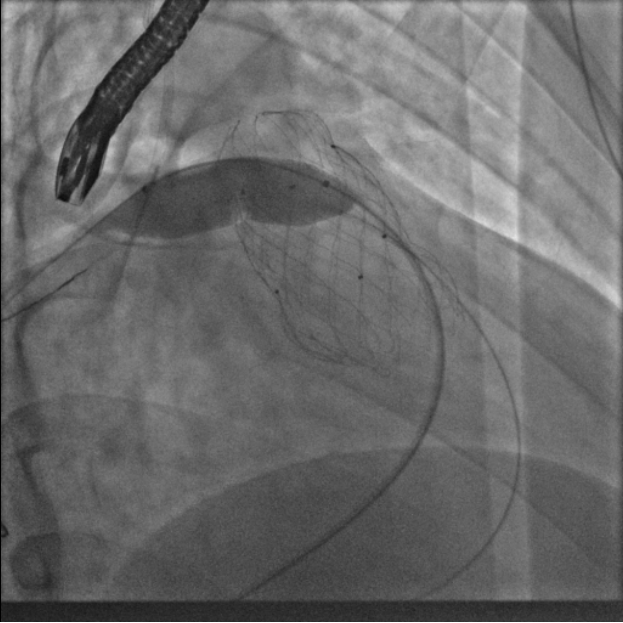

葛院士团队评估后认为,患者右肺动脉因阻挡存在狭窄,且右肺动脉与主肺动脉压差较大,具有临床意义,存在解决的必要。先后尝试Snare圈套瓣架下缘下拉法、双导管圈套瓣架上缘下拉法,但效果不理想,复测右肺动脉与主肺动脉压差仍较大,选择性右肺动脉造影仍存在右肺动脉狭窄。但考虑到患者利益,在安全操作的基础上,团队仍未放弃。拟通过将球囊送至右肺动脉开口处扩张,达到下压瓣膜支架、解除右肺动脉狭窄的效果,考虑到该操作的难点在于球囊无法顺畅到达肺瓣上目标位置,决定采用简略版PASS技术,即通过辅路送Snare至右肺动脉开口,并利用该Snare圈套住主路的Lunder quist导丝,换言之,即通过Lunder quist导丝两头发力将三尖瓣-右室流出道-右肺动脉这一扭曲的途径直线化且增强Lunder quist导丝支撑力,同时,由于Lunder quist导丝在右肺动脉处有附着力,可以避免瓣膜下移过多,如此球囊顺利通过瓣膜支架网孔进入右肺动脉,在DSA指引下逐步扩张球囊,成功使人工瓣膜支架向右心室侧移位。复查造影提示右肺动脉开口未见明显阻挡(图五),复测主肺动脉、左肺动脉、右肺动脉压力分别为32/9/19mmHg、32/7/18mmHg、29/7/17mmHg。复查肺动脉主干造影,显示人工瓣膜启闭良好,轻微瓣膜反流。最终手术疗效显著、取得令人满意的结果。

图五:通过PASS技术将球囊送至右肺动脉开口并扩张球囊、完成肺动脉瓣膜支架向心室侧移位,复查造影右肺动脉未见明显阻挡

肺瓣植入阻挡肺动脉是少见并发症,本例采用了多种技术,最终完美解决问题,为此类病人处理提供了很好经验参考。